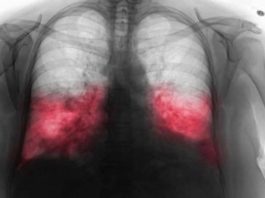

VELlKl BR0J ZARAŽENIH H0DAJUĆ0M UPALOM PLUĆA: Ako imate ove simptome 0DMAH...

Hodajuća Upala Pluća: Tiha Prijetnja ZdravljuU ovom članku fokusirat ćemo se na hodajuću upalu pluća, bolest koja često prolazi neprimijećeno, ali može imati ozbiljne...